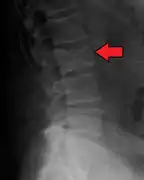

Bone pain

Illustration showing the most common site of bone lesions in vertebrae

Bone pain affects almost 70% of people with multiple myeloma and is the one of the most common symptoms.[2]:653[16] Myeloma bone pain usually involves the spine and ribs, and worsens with activity. Persistent, localized pain may indicate a pathological bone fracture. Involvement of the vertebrae may lead to spinal cord compression or kyphosis. Myeloma bone disease is due to the overexpression of receptor activator for nuclear factor κ B ligand (RANKL) by bone marrow stroma. RANKL activates osteoclasts, which resorb bone. The resultant bone lesions are lytic (cause breakdown) in nature, and are best seen in plain radiographs, which may show "punched-out" resorptive lesions (including the "raindrop" appearance of the skull on radiography). The breakdown of bone also leads to the release of calcium ions into the blood, leading to hypercalcemia and its associated symptoms.

The diagnostic examination of a person with suspected multiple myeloma typically includes a skeletal survey. This is a series of X-rays of the skull, axial skeleton, and proximal long bones. Myeloma activity sometimes appears as "lytic lesions" (with local disappearance of normal bone due to resorption). And on the skull X-ray as "punched-out lesions" (pepper-pot skull). Lesions may also be sclerotic, which is seen as radiodense.[52] Overall, the radiodensity of myeloma is between −30 and 120 Hounsfield units (HU).[53] Magnetic resonance imaging is more sensitive than simple X-rays in the detection of lytic lesions, and may supersede a skeletal survey, especially when vertebral disease is suspected. Occasionally, a CT scan is performed to measure the size of soft-tissue plasmacytomas. Bone scans are typically not of any additional value in the workup of people with myeloma (no new bone formation; lytic lesions not well visualized on bone scan).